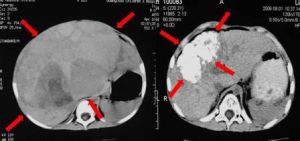

血清甲胎蛋白的檢測對肝癌的診斷極為重要。90%~100%為陽性,比成人病例更高(成人為70%~80%陽性)。許多生物化學物質如蛋白、脂質、酶等皆由肝臟產生或在肝臟中進行代謝,故血膽固醇、乳酸脫氫酶(LDH)、白蛋白、球蛋白、鹼性磷酸酶、膽紅質等檢查均能反映肝臟功能,均屬必要。血清鹼性磷酸酶常增高,這對肝癌的診斷亦頗有幫助。超音波檢查、核素肝掃描對本病診斷均有幫助。CT、MRI(磁共振影像診斷)對診斷均有參考價值。